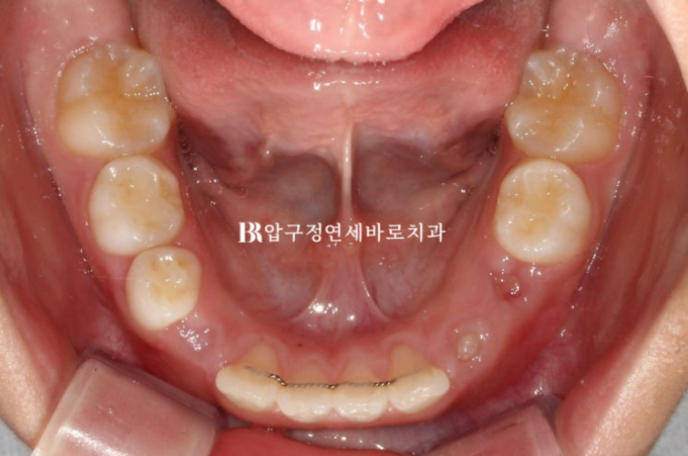

입천장은 좁고 앞니는 삐뚤합니다.

23.09

좁았던 입천장 악궁이 넓어졌고 앞니 배열이 가지런해졌습니다.